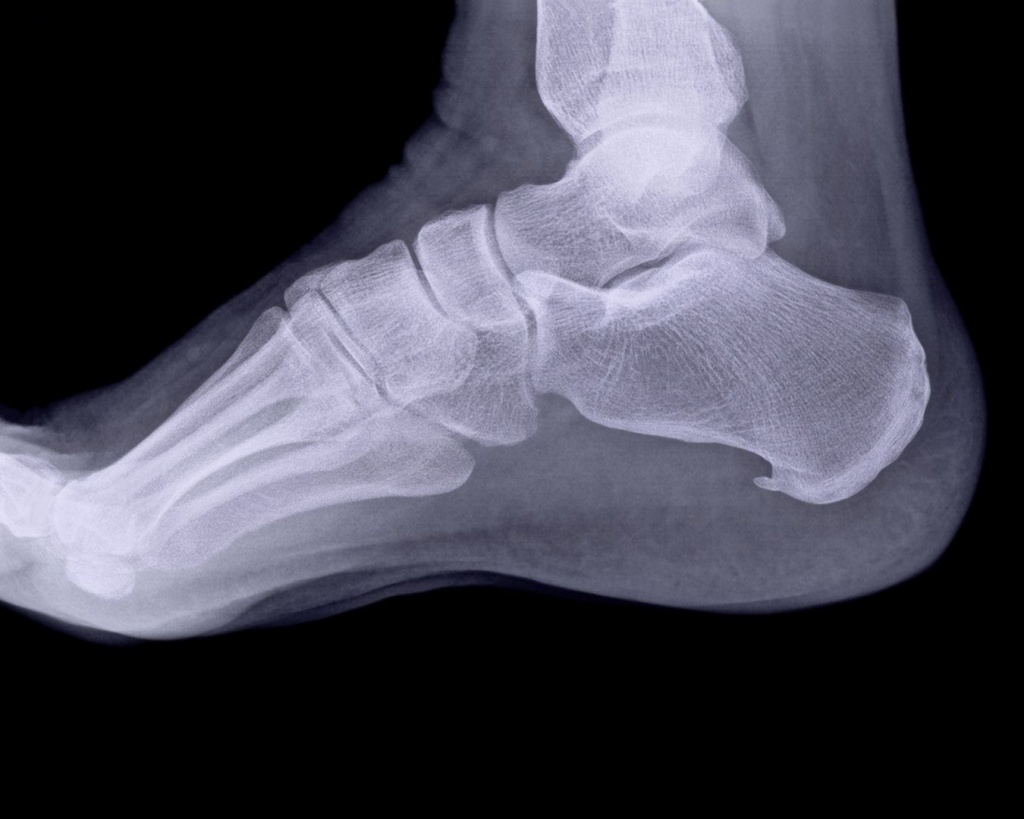

Біль у п’яті – це не дрібниця, яку варто терпіти. Він може виникати раптово після травми, поступово наростати при ходьбі або турбувати щоранку після сну. У таких випадках рентген п’яткової кістки є базовим і надзвичайно інформативним методом діагностики, який дозволяє швидко з’ясувати причину болю та обрати правильну тактику лікування.

Рентгенографія п’яткової кістки дає можливість оцінити стан кісткових структур, побачити переломи, тріщини, деформації, кісткові розростання та наслідки хронічних навантажень. Обстеження займає кілька хвилин, не потребує спеціальної підготовки й дозволяє отримати результат уже в день звернення.

Знімки виконуються у кількох проєкціях, що дозволяє максимально точно оцінити стан п’яткової кістки та уникнути помилок у діагностиці.

Цифровий формат дозволяє збільшувати окремі ділянки зображення, оцінювати навіть незначні зміни та передавати результати для подальших консультацій.